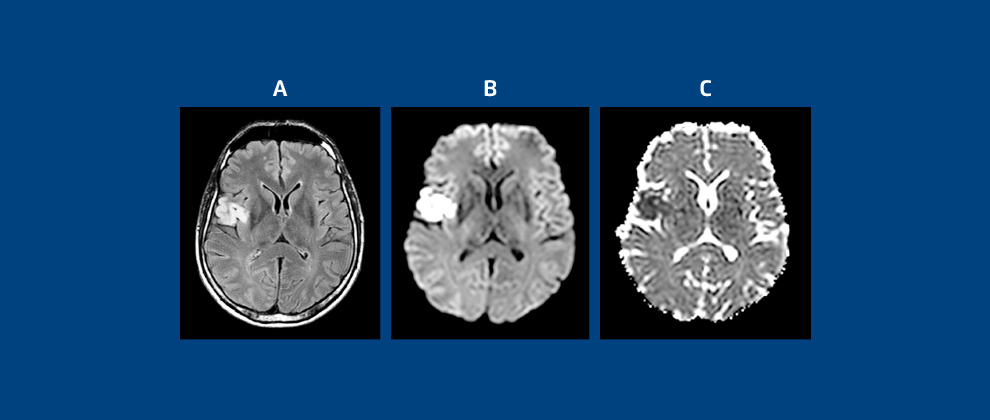

Figura 1: quadros A, B e C representam um infarto isquêmico recente.

O quadro A, em Flair T2W, mostra lesão hiper intensa opercular frontal direita; quadro B, em Imagem por Difusão (DWI), mostra área de difusão restrita, com “brilho” por edema citotóxico; quadro C, em mapa de Coeficiente de Difusão Aparente (ADC) com sinal baixo, é compatível com infarto isquêmico recente.